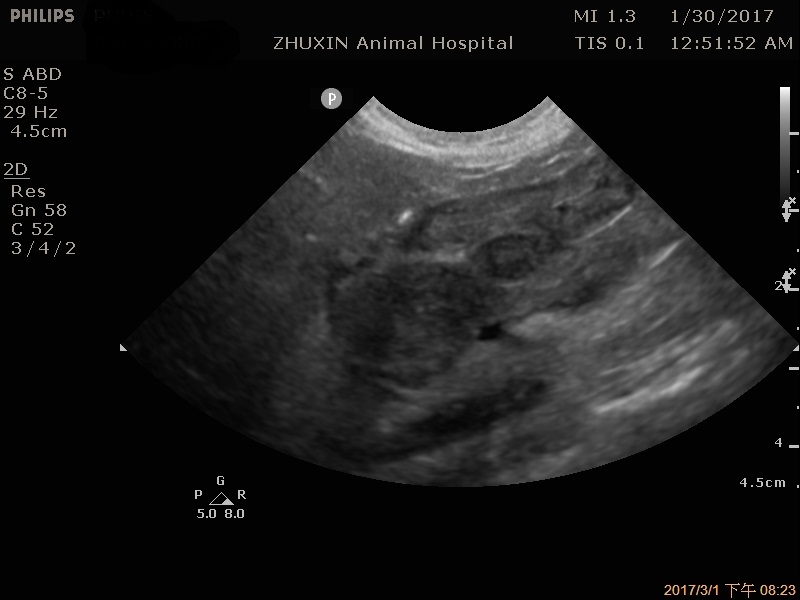

慢性消瘦、嘔吐的老貓,在他院反覆檢查一直找不出病因,經由超音波掃描終於發現問題,胃部有多發性團塊,強烈懷疑淋巴瘤,因貓咪已經非常虛弱,最後決定安寧治療。